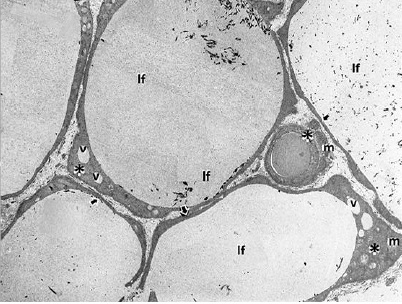

Las células foliculares del Grupo Control (Fig.8) muestran las características citotípicas de un epitelio cúbico, con núcleo redondeado con cromatina densa. Se evidencian numerosas microvellosidades apicales cortas y en el citoplasma se observan abundantes mitocondrias y retículo endoplásmico rugoso.

En las células foliculares del Grupo Expuesto se evidencian disminución de la altura del epitelio folicular, núcleos de contornos irregulares, retracción nuclear con aumento de la dimensión de la cisterna perinuclear y cromatina dispersa. Es notable la disminución de las organelas celulares en el citoplasma folicular. En algunas muestras del Grupo Expuesto se observó marcado deterioro tisular con pérdida de la organización celular que en algunos casos degeneró en atrofia celular, además de infiltración de tejido fibroso en los espacios interfoliculares. Otros hallazgos consistentes fueron la presencia de vacuolas intracitoplasmáticas y ausencia de vellosidades apicales (Figs. 9 A, B, C y D).